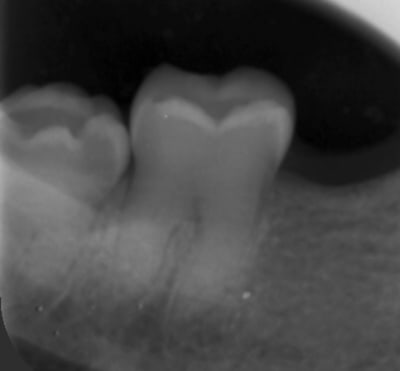

Radio 36

405399a3 cf02 4879 a549 5c8b6158e26b jozk2u - Eugenol